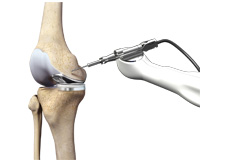

Knee Arthoscopy

Knee Arthroscopy is a common surgical procedure performed using an arthroscope, a viewing instrument, to diagnose or treat a knee problem. It is a relatively safe procedure and most of the patients are discharged from the hospital on the same day of surgery.

Minimally Invasive Knee Joint Replacement

Total knee replacement is a very successful surgical treatment for knee arthritis. Over the years, minimally invasive knee replacement surgical techniques have been developed to lessen tissue trauma and improve patient outcomes.

Robotic Assisted Knee Replacement

Robotic-assisted knee replacement surgery is an alternative to the conventional knee replacement procedure. It is performed using robotic-arm technology that allows your surgeon to precisely perform the surgery through a smaller incision as compared to traditional surgery.